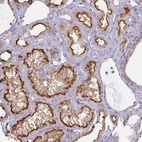

Immunohistochemical staining of human kidney shows strong luminal membranous positivity in cells in tubules.